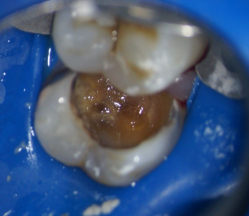

Пример осложненного кариеса контактной поверхности , в данном случае потребуется лечение корневых каналов зуба ,укрепление зуба штифтом и последующие покрытие зуба коронкой. Вот такой печальный итог небрежного отношения к своему здоровью.

Видна значительная потеря твердых тканей зуба в результате кариозного процесса и как следствие необходимость сложного и затратного лечения.